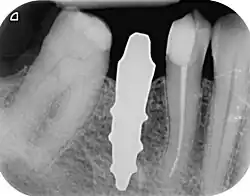

A root-analogue dental implant (RAI) – also known as a truly anatomic dental implant, or an anatomical/custom implant – is a medical device to replace one or more roots of a single tooth immediately after extraction.[1] In contrast to common titanium screw type implants, these implants are custom-made to exactly match the extraction socket of the specific patient. Thus there is usually no need for surgery.[2]

As the root analogue dental implant matches the dental alveolus (tooth socket) it can only be placed immediately after the tooth extraction. If the tooth has been already lost and the soft and hard tissue is already healed, an RAI can no longer be placed.[1]

RAIs are custom made to perfectly fit the tooth socket of a specific patient immediately after tooth extraction. Therefore every implant is unique. As an optimised root-form it is much more than a simple 1:1 replica of a tooth. Since it exactly fills the gap left after the tooth is extracted, surgery is rarely needed. The implant can be produced from a copy of the extracted tooth, an impression of the tooth socket, or from a CT scan or CBCT scan.[7] The advantage of a CBCT scan is that the implant can be produced before extraction. With the former methods, it takes one or two days to fabricate an implant.

- Natural form: a custom milled anatomic implant replicates the natural form of a tooth, so it simply fits into the tooth socket. Like the original tooth, a root analogue implant can have single- and multi-rooted forms.